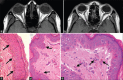

Vogt-Koyanagi-Harada (VKH) syndrome is an immune-mediated granulomatous disease which affects melanin-rich organs like eyes, skin, nervous system, and ears. Neurological and auditory manifestations usually precede the involvement of other sites. Patients may manifest with "complete" or "incomplete" syndrome. We report two patients who presented with acute headache and impaired vision. Fundus examination revealed optic disc hyperemia and exudative retinal detachment which provided a clue for the diagnosis at the bedside. Fundus fluorescein angiogram (FFA) revealed abnormal dye leakage, whereas B scan showed choroid thickening. Cerebrospinal fluid (CSF) pleocytosis contrasted with unremarkable brain magnetic resonance imaging and lack of meningeal signs. Melanophagocytosis was evidenced by melanin-laden macrophages in CSF and skin biopsy. This finding is specific for VKH syndrome and helps to clinch the diagnosis even when the complete syndrome is not present cross-sectionally. VKH syndrome should be suspected in patients with aseptic meningitis if tests for common infectious and immune-mediated diseases are negative.

Figures